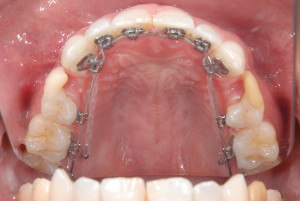

裏側(舌側)矯正で内側に埋入

上記のようなシンプルなのもあれば上顎の内側(口蓋部)に2本アンカースクリューを埋入して、そのアンカースクリューにアームとなるワイヤーなどの矯正装置を装着して固定源にするタイプもあります。こちらは歯と離れていますので、アンカースクリューのネジ部が歯の根にぶつかる事がなく、遠心移動や正中を合わせるなど様々な動的処置に対応が可能です。

シンプルなものよりは当然舌感は悪くなります。

現在ではPLASやアイステーション(i-station)などを主に用います。